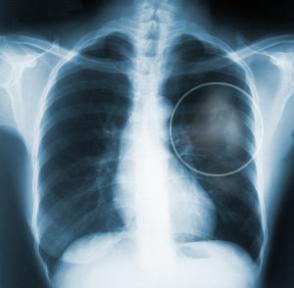

Πώς γίνεται η διάγνωση;

– ακτινογραφία θώρακα

– αξονική τομογραφία

Η διάγνωση βασίζεται στο οικογενειακό, ατομικό και επαγγελματικό ιστορικό του ασθενούς, στην κλινική εξέταση και στις συμπληρωματικές εξετάσεις (π.χ. εξέταση των πτυέλων, ακτινογραφία του θώρακα, αξονική τομογραφία του θώρακα και βιοψία).